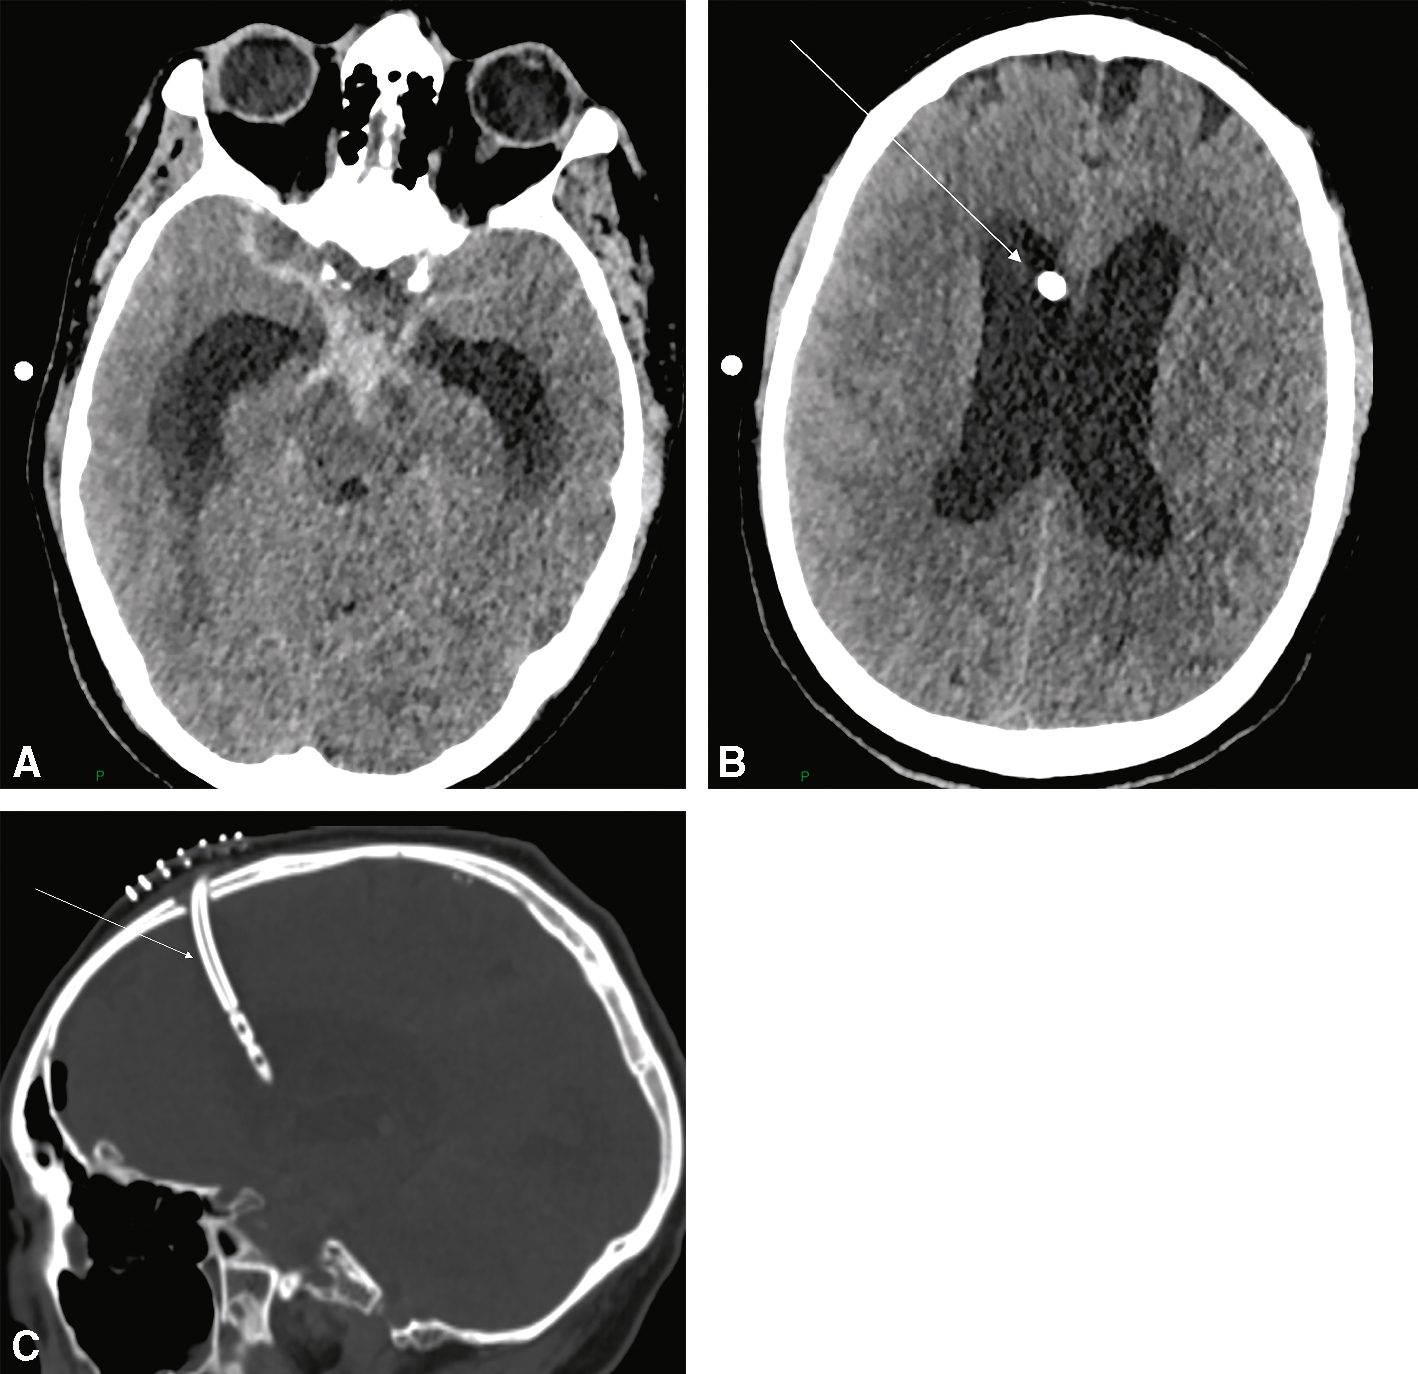

Fig. 29.1

Scanner cérébral sans injection (coupe axiale) montrant une hyperdensité spontanée des citernes de la base, des deux vallées sylviennes.Image de scanner cérébral en coupe axiale, réalisée sans injection de produit de contraste, révélant une hyperdensité spontanée localisée dans les citernes de la base ainsi que dans les deux vallées sylviennes. Cette hyperdensité, visible sous forme de zones blanches au sein des espaces sous-arachnoïdiens, évoque fortement la présence de sang, suggérant une hémorragie méningée aiguë, très probablement d’origine anévrismale. La symétrie des structures cérébrales profondes est globalement respectée, mais la densité accrue dans ces régions clés impose une prise en charge rapide, car elle témoigne d’un saignement actif dans les espaces cérébro-méningés.

Elle est liée à l’obstruction des voies de circulation du LCS (fig. 29.5A).

• Son traitement consiste en la mise en place d’un cathéter de dérivation ventriculaire externe (fig. 29.6).

Fig. 29.6

Scanner cérébral montrant la pose d’un cathéter de dérivation ventriculaire externe (DVE).

A. Scanner cérébral en coupe axial montrant une HSA des citernes de la base avec dilatation des cornes temporales des ventricules latéraux. B. Scanner cérébral en coupe axial montrant une DVE (flèche) positionnée dans la corne frontale du ventricule latéral droit. C. Scanner cérébral en coupe sagittale montrant la trajectoire de la DVE (flèche).Les trois coupes tomodensitométriques (axiales et sagittale) montrent l’emplacement d’un cathéter de dérivation ventriculaire externe. Sur les vues axiales, la première image montre une dilatation des ventricules latéraux, en particulier des cornes frontales, suggérant une hydrocéphalie active. La seconde image met en évidence le cathéter placé dans le ventricule droit, bien centré sans déviation, avec son extrémité visible au sein du liquide cérébrospinal. La coupe sagittale confirme le trajet du cathéter depuis le scalp jusqu’à la cavité ventriculaire. Aucun signe d’hémorragie, de malposition ou de complication immédiate n’est visible.